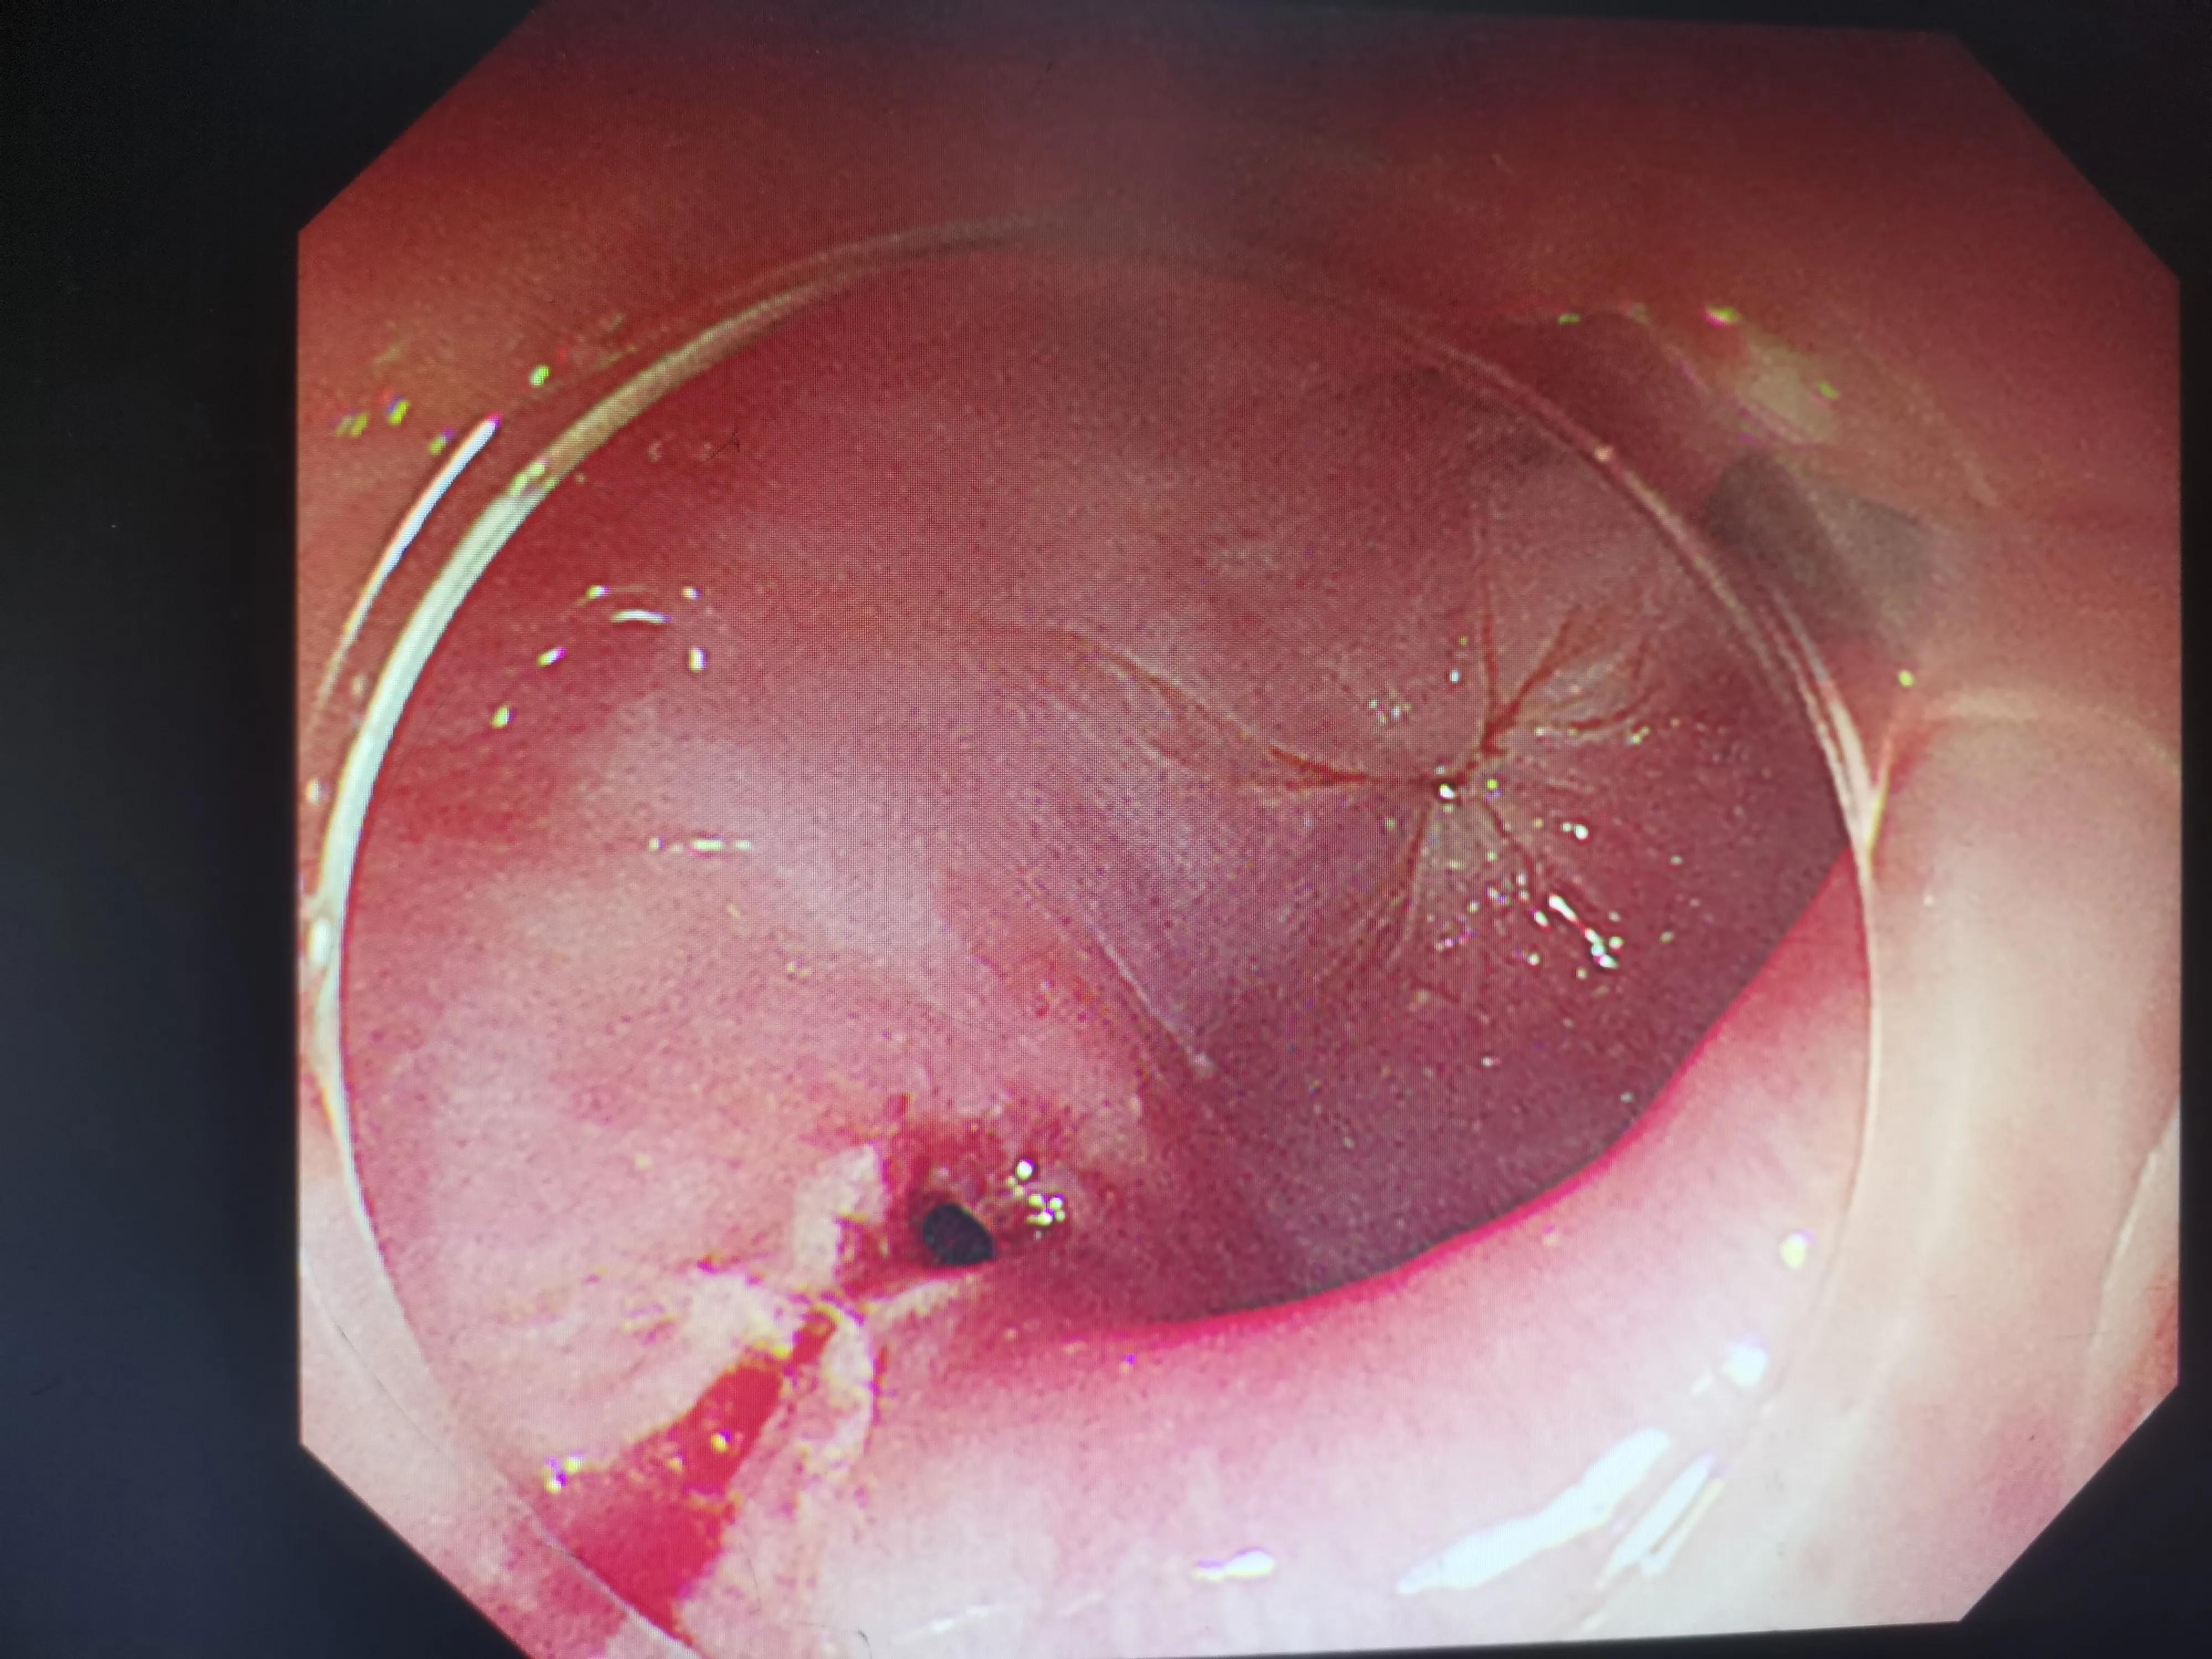

我所说的手术就是插入一根胃镜进入到食管,找到异物后再用异物钳给取出来。说着容易,做着难。我跟护理李老师经常搭手取异物,非常熟悉了。我很快熟练操作胃镜进入食道,不出所料首先发现的是食管内大量的食物残渣,清理完这些残渣后才发现食管下方卡了一根非常坚硬的鸡刺骨,我小心操作胃镜,轻轻用异物钳夹住鸡骨头,调整好角度就取出来了。只可惜,鸡骨头比较锋利的那一端已经刺破了食管壁,留下了一个破口——食管穿孔!